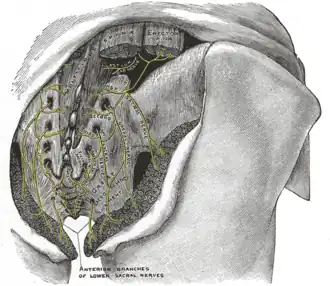

The posterior divisions of the sacral nerves

The posterior divisions of the sacral nerves -